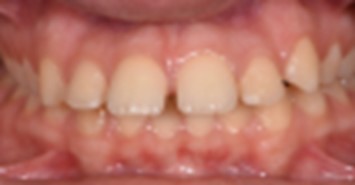

In order to emphasize one of the major indications of skeletal anchorage with mini implants, a clinical case was selected. A young teenage patient (Figure 1, Figure 2, Figure 3, Figure 4), with a severe overjet, flared upper incisors with spacingand a convex profile was reffered to our dental office. Treatment objectives were established from the beggining: retrusion of the upper anterior teeth, overjet and overbite correction, space closure and obtaining a better occlusion. Anchorage needs were evaluated. Absolute anchorage was needed in order to obtain upper dental retrusion without mesial movement of the posterior teeth. Two mini implants were placed bilaterally, in a labial position, between the second premolars and upper first molars. Both mini plates and mini implants provide a predictable result in this case but since mini implants are more easy to place and provide a higher degree of comfort, this option seemed more suitable. In this way, the need for other anchorage devices, such as a palatal arch or headgear was eliminated. The upper incisors and canines can be now distalized and intruded, after the upper premolar extraction.

Figure 2.Initial intraoral view of the case before orthodontic treatment – occlusal view.

Figure 3.Initial intraoral view of the case before orthodontic treatment – occlusal view.